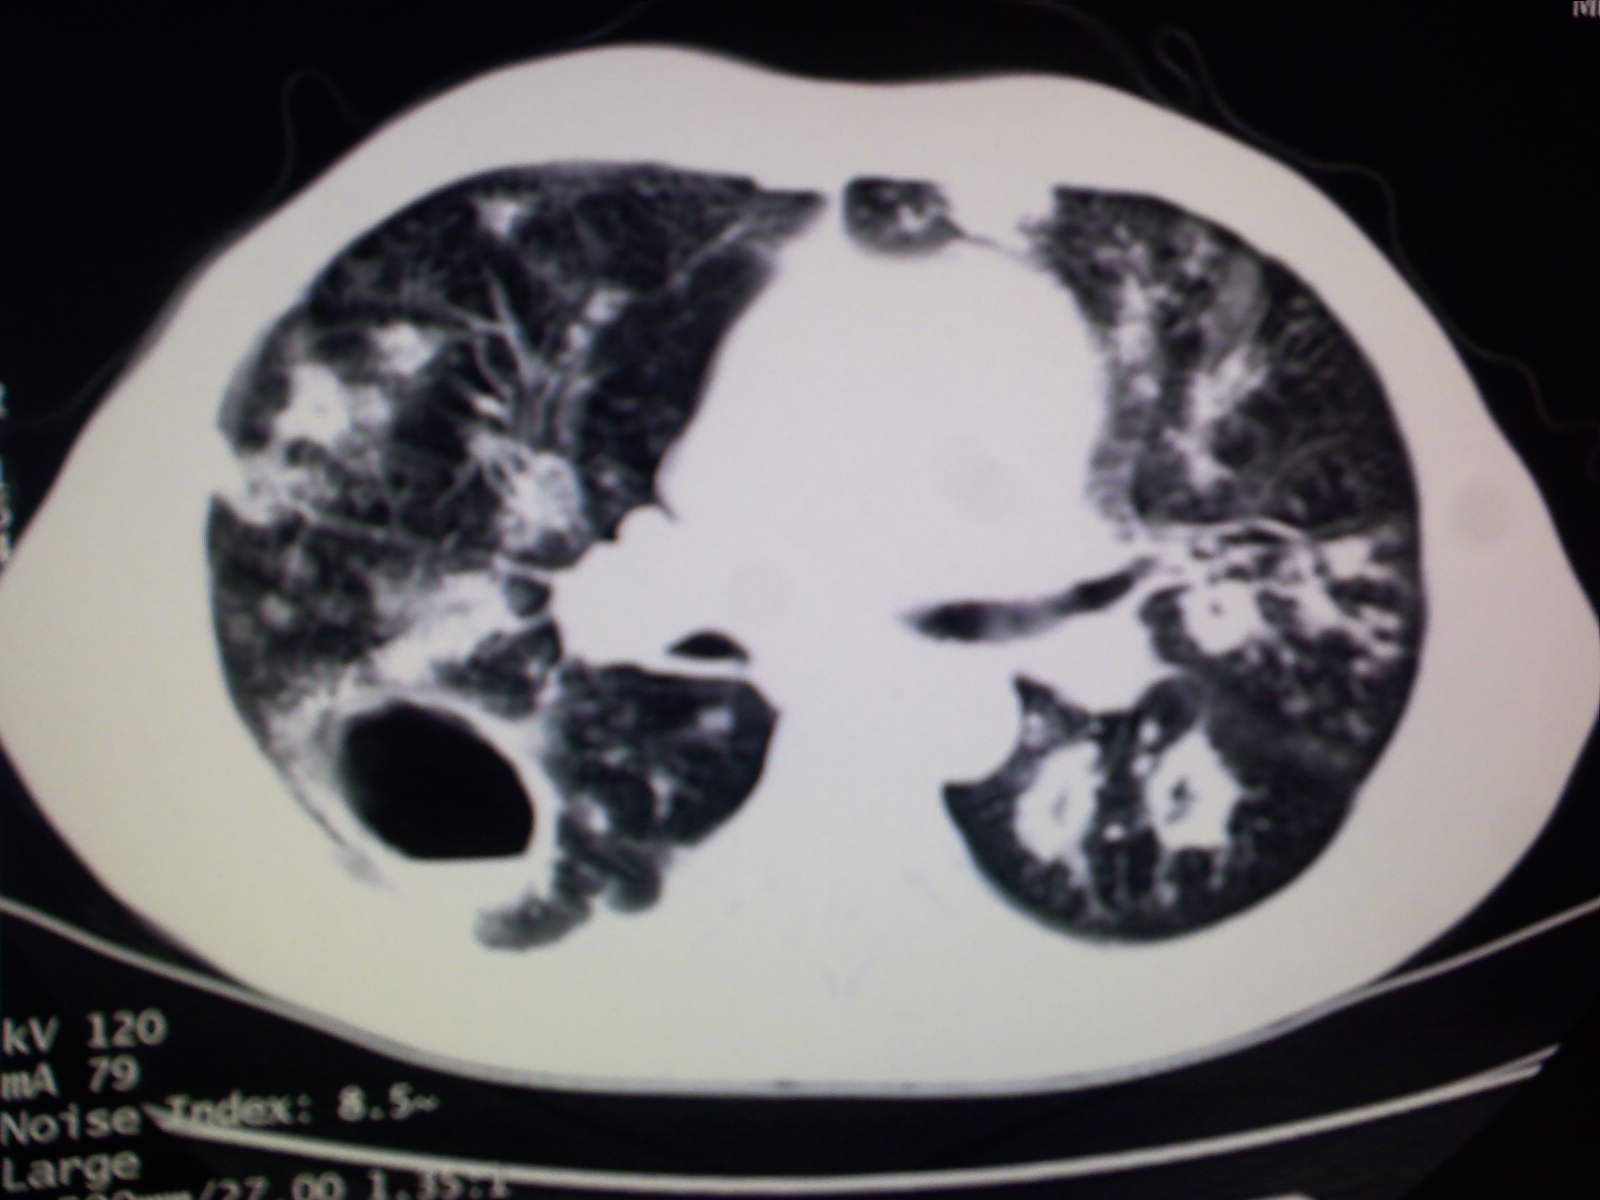

以下是引用卜一在2009-4-11 15:50:00的发言:[br]双肺继发性肺结核伴空洞形成,不排除合并霉菌感染!(病灶呈多形态 多特征 散在分布)。另:合并支气管扩张征伴感染!

以下是引用主力军在2009-4-11 15:55:00的发言:[br]两肺继发性肺结核可能性大。

以下是引用康鹏在2009-4-11 16:30:00的发言:[br]双肺继发性肺结核伴空洞形成合并感染[br]支气管扩张合并感染